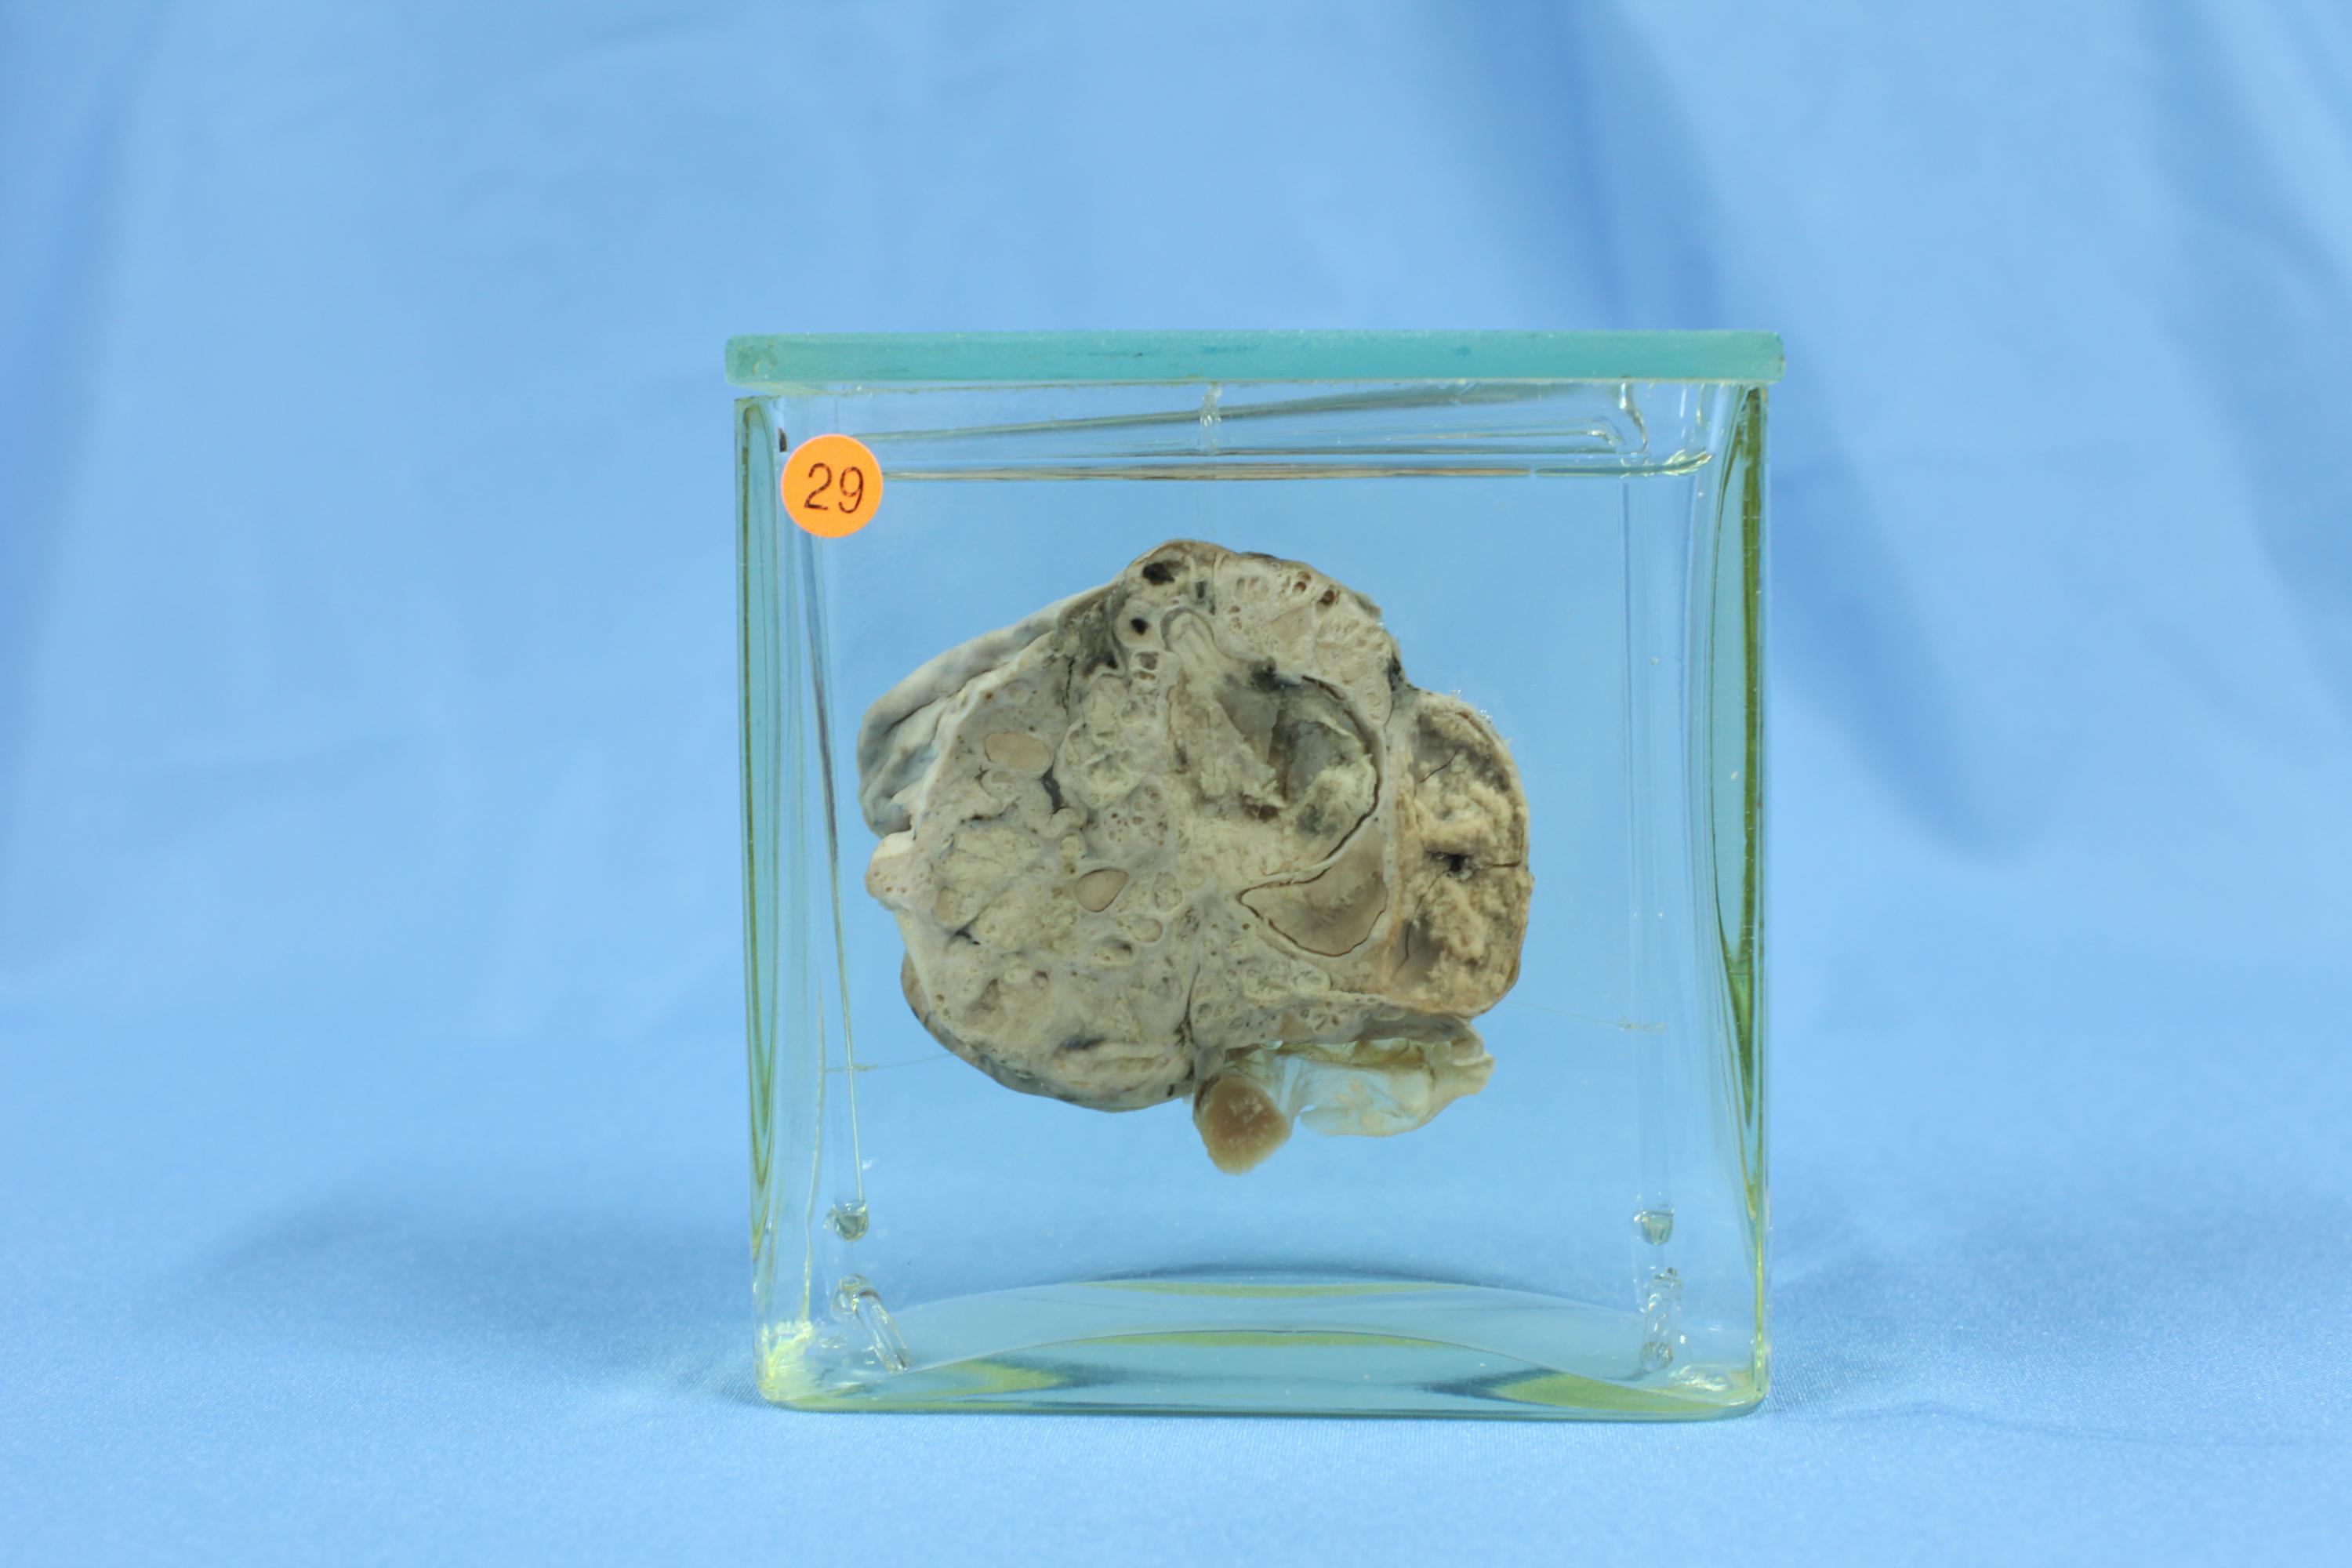

生殖疾病42-29. 卵巢转移性粘液腺瘤(63-1614)

肿瘤侵犯卵巢,直径 6cm,灰黄色,表面(标本背面)呈结节状隆起。切面见肿瘤质实,可见透亮胶冻样物分散在实质组织中,局部组织出血坏死。